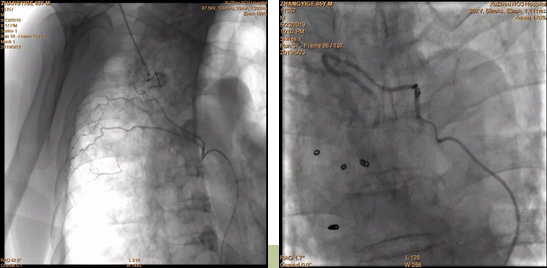

介入科李鵬飛(fēi)醫生(shēng)見(jiàn)到(dào)張大(dà)爺時(shí),他(tā)的(de)情況已相(xiàngβ)當危險,鮮血不(bù)斷從(cóng)他(tā)口鼻噴出來(lái),人(rén)已經昏迷不(bù)醒,而α張大(dà)爺的(de)血壓、血氧飽和(hé)度數(shù)值一度極低(dī)。分(fēn)析患者的(de♥)胸部CT 後,李鵬飛(fēi)醫生(shēng)判斷患者是(shì)支氣管擴張誘發的(de≤)咯血,需要(yào)緊急進行(xíng)血管造影(yǐng),查找出血點并進行(xíng)栓塞止血。通(tōng)過造影(yǐng)發現(xiàn),張大(dà)爺肺部&果然有(yǒu)血管破裂。當即,李鵬飛(fēi)醫生(shēng)利用(yòng)一根纖£細的(de)導管和(hé)栓塞材料徹底封堵了(le)出血點,經過造影(yǐng)複查,止血點封堵成功•,患者轉危為(wèi)安。

左圖:右側肋間(jiān)動脈參與出血;

右圖:右支氣管動脈栓塞彈簧圈後。